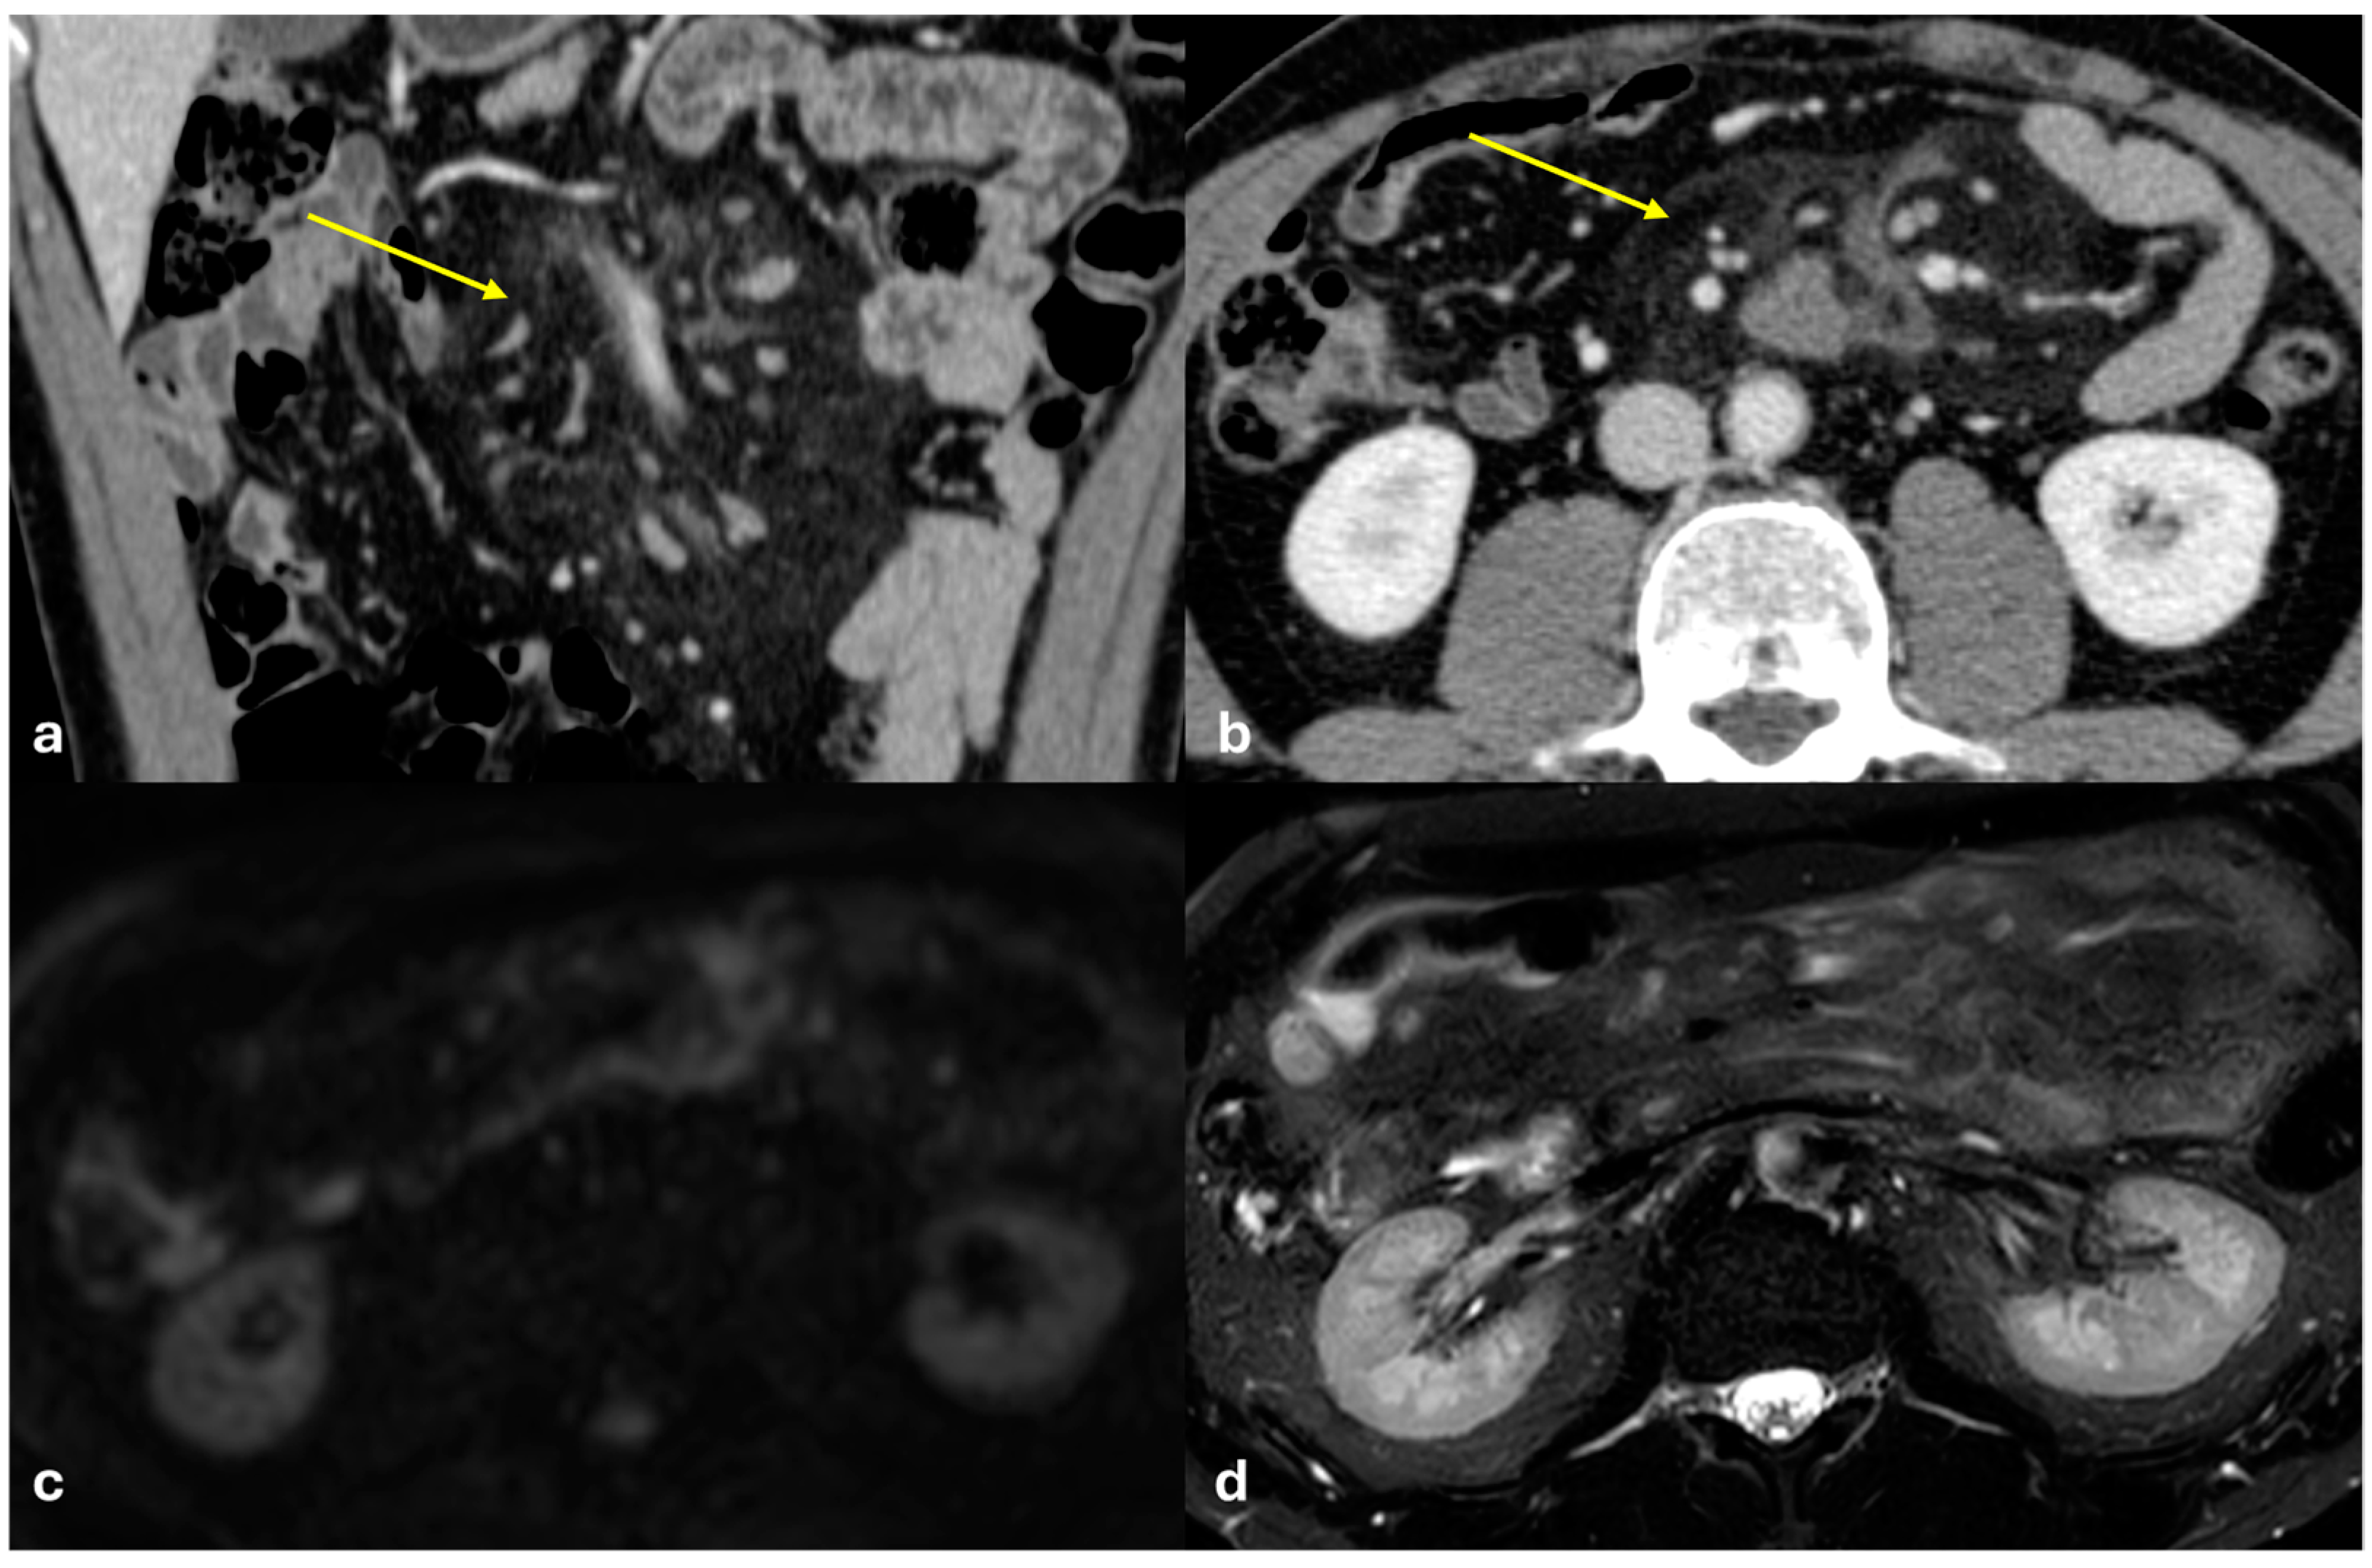

- Micro-nodular pattern: micro-nodules with a diameter ≤ 5 mm (Figure 1);